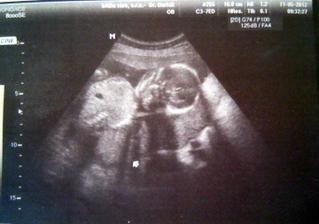

11.5. ultrazvuk ve 20tém týdnu - všechno OK - podle paní doktorky jsme o týden starší. Miminko sebou krásně házelo, že byl poblém ho vyfotit. Jinak se nám nechtělo mimčo ukázat, jestli je to opravdu kluk. Musíme si ještě počkat 🙂

17.5. ultrazvuk srdíčka - miminko v pořádku, potvrzen chlapeček